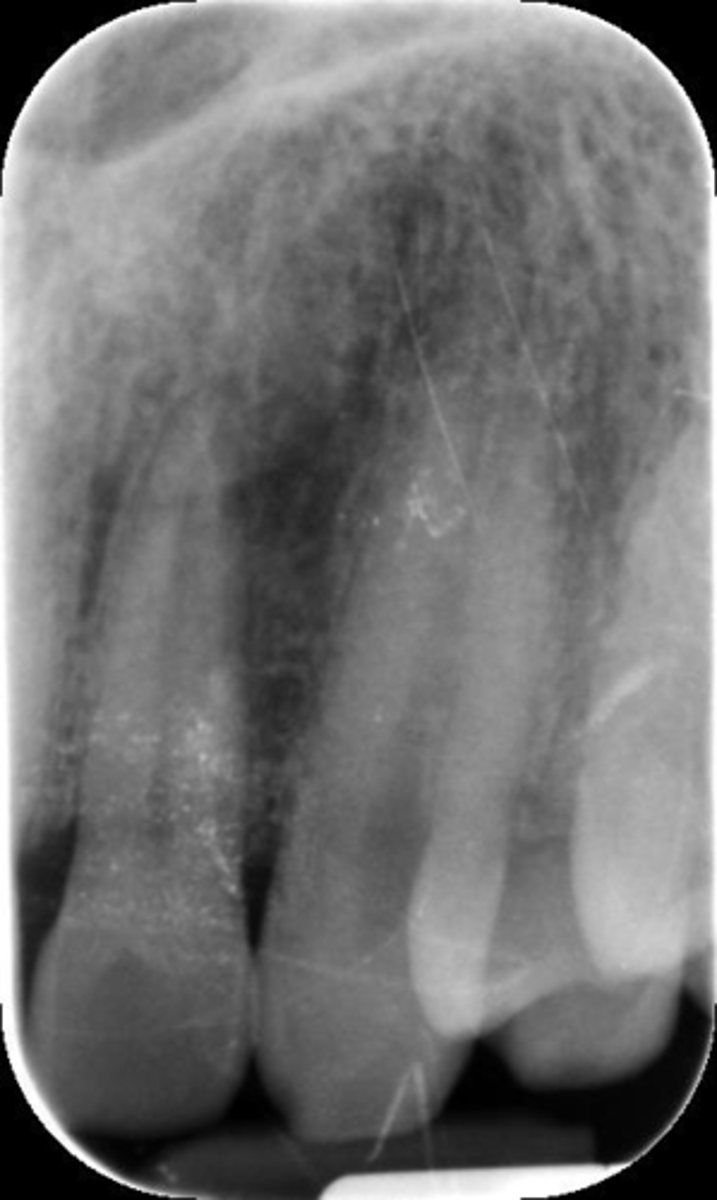

Underexposed

What is this error?